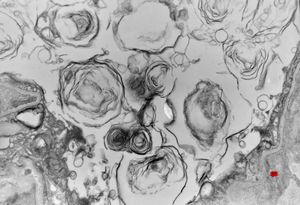

F, 2m. | surfactant deficiency